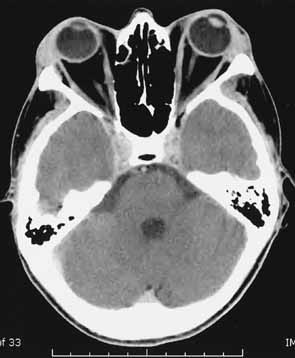

The increased orbital volume is usually due to both extraocular muscle and orbital fat expansion; however, patients younger than 40 years of age are more likely to exhibit orbital fat enlargement in the absence of muscle enlargement, whereas patients over 70 years are more prone to severe, fusiform muscle enlargement without significant changes in orbital adipose tissue volume.49 Forbes et al.11 reported enlargement of the fat compartment in 46% of patients with TO, whereas 8% had increased fat compartments with normal muscle volumes (Fig. 4).

Fig. 4 Axial CT scan of patient with thyroid orbitopathy, extreme proptosis, and no clinical evidence of optic neuropathy. Note the increase in orbital fat volume without significant extraocular muscle enlargement. In this case axial proptosis has allowed spontaneous decompression of increased orbital volume.

The pattern of muscle enlargement on CT parallels that seen clinically. The inferior rectus is the most commonly involved, followed by the medial rectus, superior rectus, and lateral rectus. Other findings include proptosis and anterior prolapse of the orbital septum due to excessive orbital fat and muscle swelling (see Fig. 4).76 Also, lacrimal gland enlargement and bone remodeling without erosion can occur.75 Patients at risk for developing optic neuropathy may also have severe apical crowding, a dilated superior ophthalmic vein, and anterior displacement of the lacrimal gland.68 Of these, apical crowding is the most sensitive indicator for the presence of optic neuropathy (Fig. 5A).56 Both axial and coronal CT cuts should be obtained; the coronal plane is needed to assess the enlargement of the extraocular muscles at the apex (see Fig. 5B).